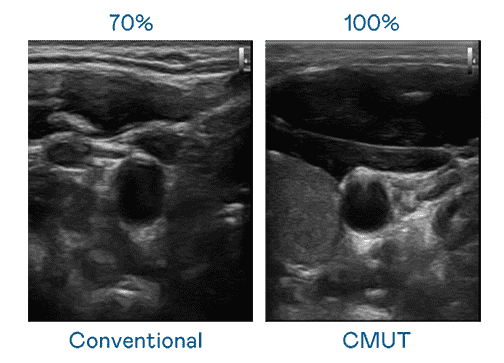

CMUT 技术是一种用电容式微机电元件来产生超音波讯号的技术。。。。与传统 PZT 压电式技术相比,,,,CMUT 频宽增加 30%,,更宽频的超音波讯号让影像解析度大幅提升,,,是实现高影像品质医疗超音波扫描、、促进精准医疗发展的关键技术。。。。

大频宽带来超清晰影像

超音波影像的解析度高低,,,,首先取决于探头能发出的讯号频宽。。。。巨星国际 CMUT 可提供高清晰的超音波讯号,,提供高频宽、、、、高灵敏度、、、影像纹理细节更高的超音波影像,,,协助医护人员缩短影像判读时间及利用精准的医疗影像进行诊断。。。。